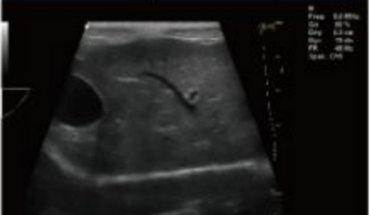

Rich Clinical Application Function

- Speckle Nosie Removal Technology

- Pulse Inversion Tissue Harmonic Imaging Technology(iTHI)